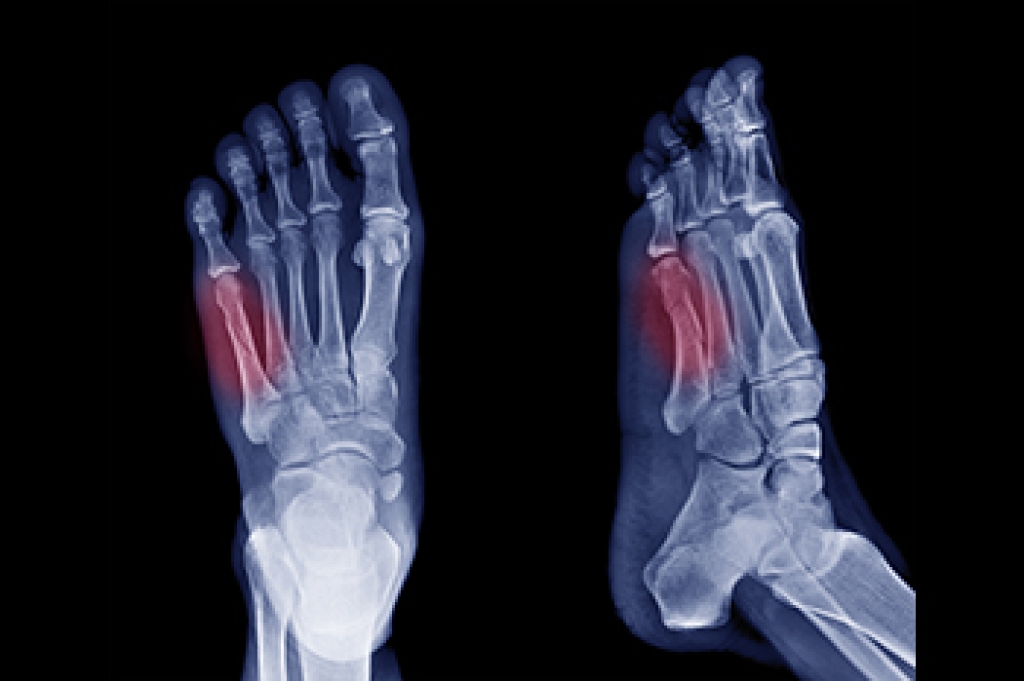

If you have any questions, please feel free to contact our office located in Lehi, UT . We offer the newest diagnostic and treatment technologies for all your foot care needs.